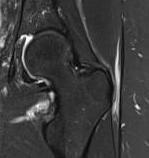

MRI

Trochanteric bursitis

Abductor tendinopathy

Edema around trochanteric bursa on T2 MRI